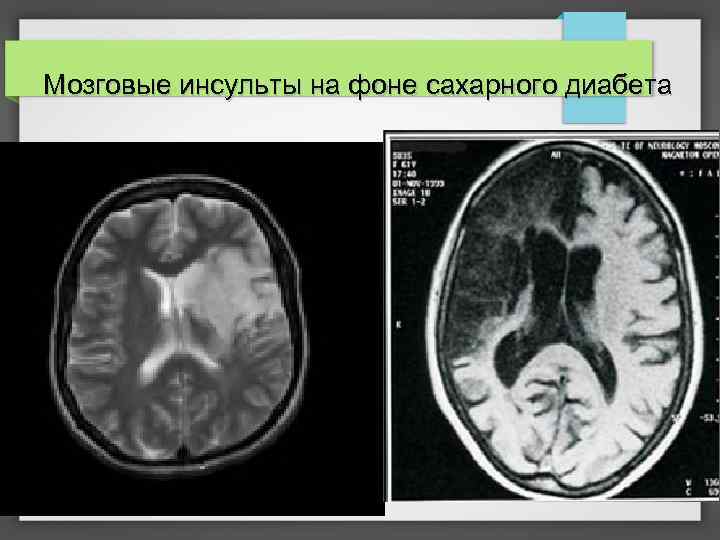

Мозговые инсульты на фоне сахарного диабета